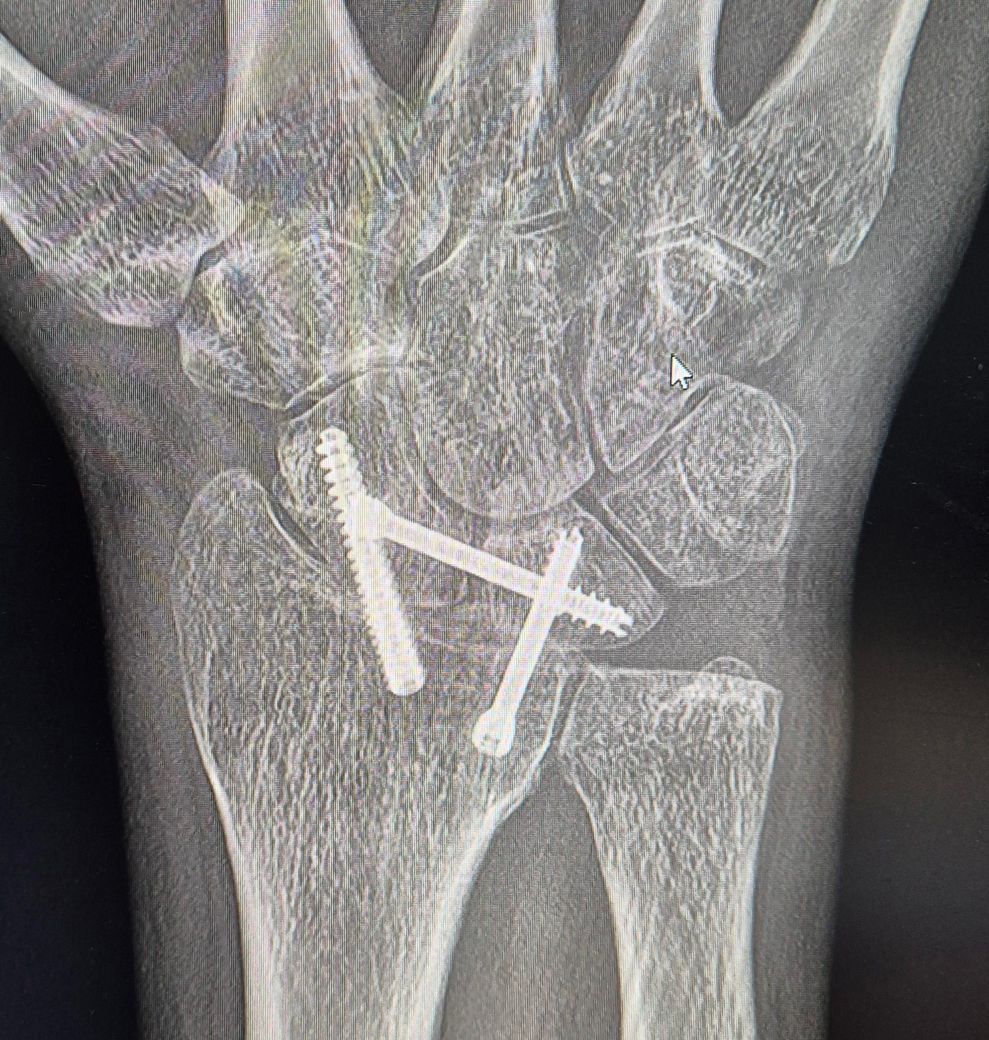

손목관절장애로 장애등급 신청했는데 이정도면 가능할까요?(엑스레이 첨부)

장애등급심사 제출용으로 병원에서 cd에 복사해온 자료입니다.

현재 손목가동 범위 180도중에 30도만 가능한 상태고 신전과 요측편위는 0도고 굴곡 20도 척측편위 10도 입니다.